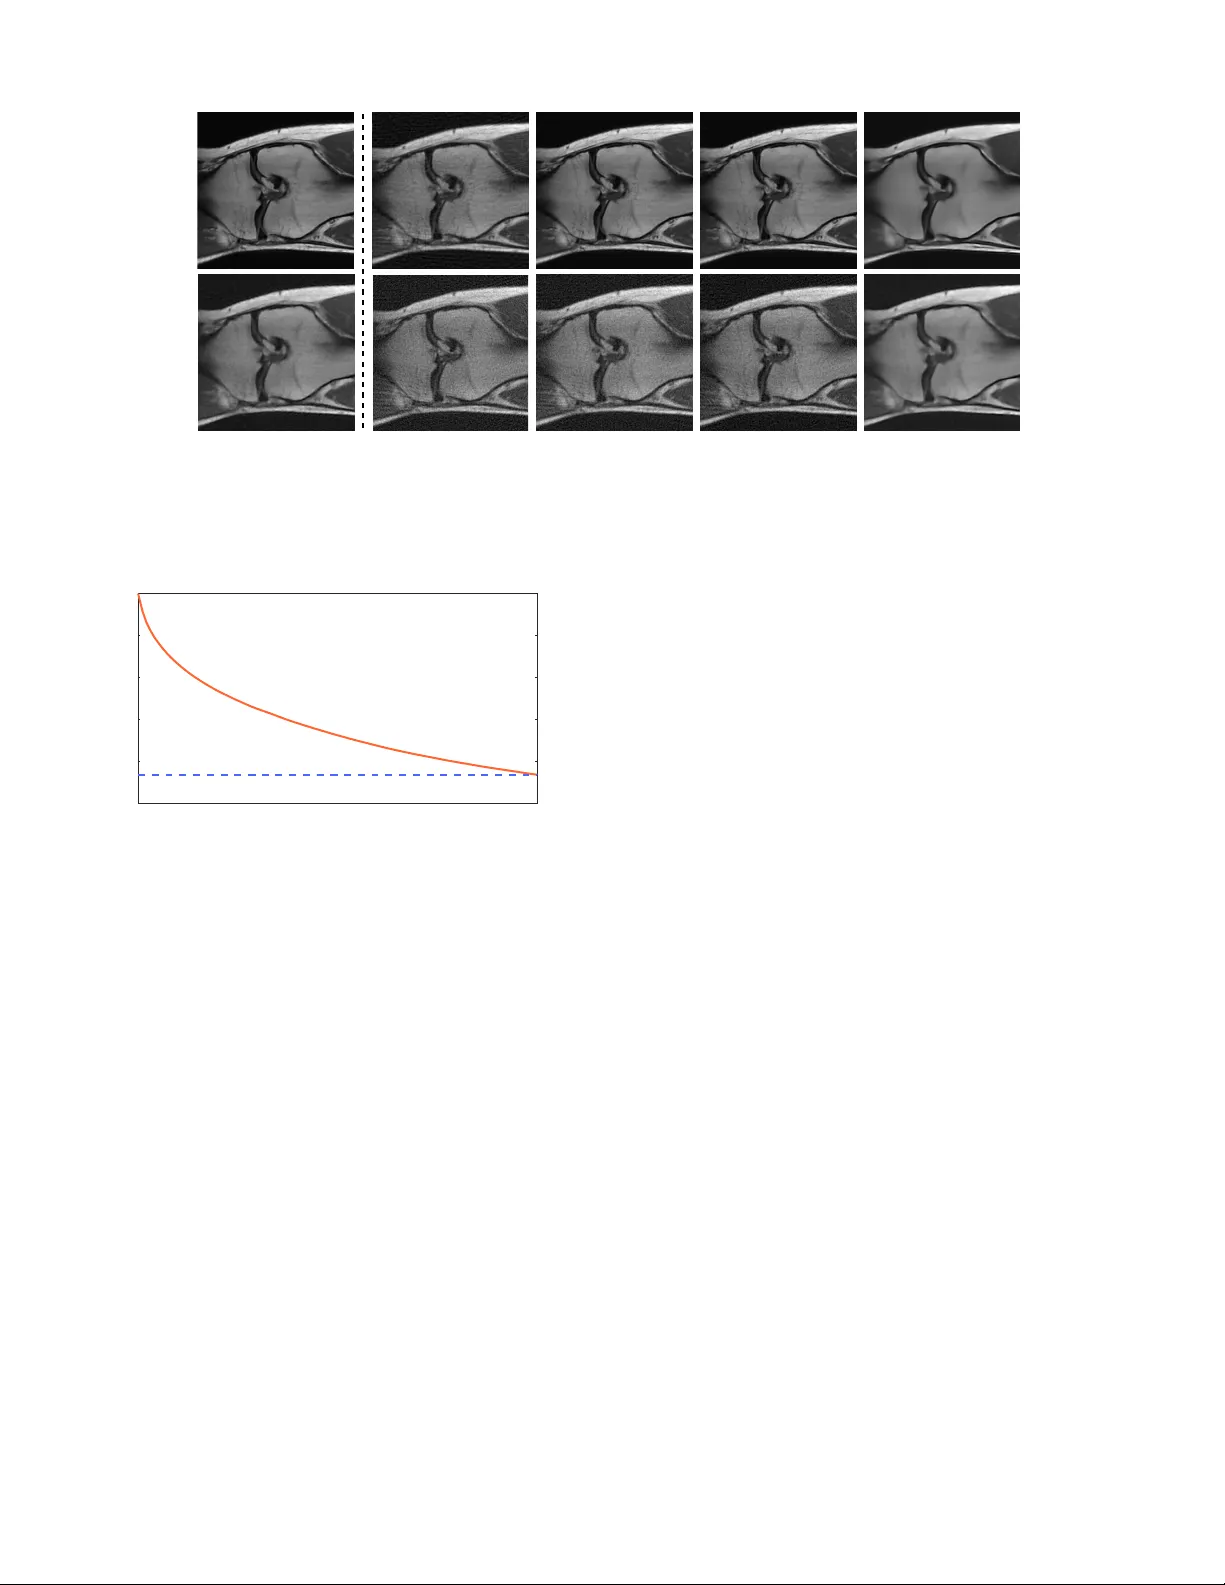

We consider the problem of estimating a vector from its noisy measurements using a prior specified only through a denoising function. Recent work on plug-and-play priors (PnP) and regularization-by-denoising (RED) has shown the state-of-the-art perfo…